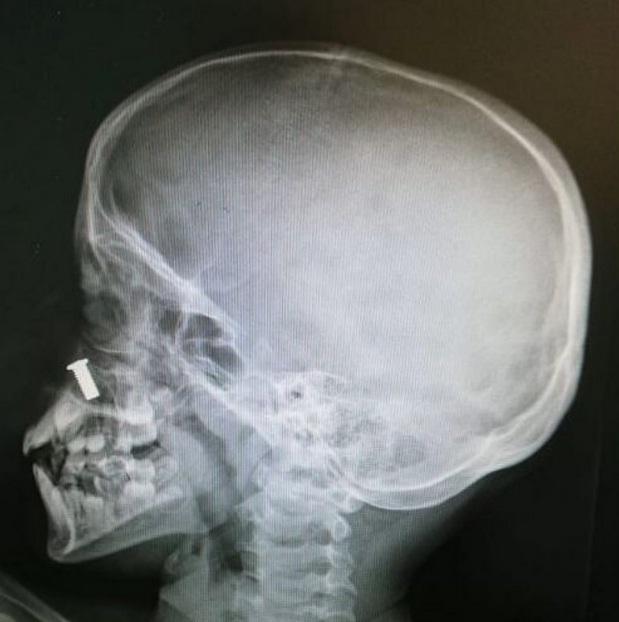

جح فريق طبي داخل مستشفى البدائع العام في استخراج مسمار كان بداخل أنف طفل، من غير إجراء أي جراحة، دون أن يتأثر الطفل جراء ذلك بالرغم من الحجم الكبير للمسمار.

واتجه الطفل البالغ من العُمر (9 أعوام) مع ذويه إلى قسم الطوارئ، حيث يُعاني من آلام كبيرة في الأنف، بسبب وجود مسمار كبير الحجم، ليتعامل فريق الأطباء مع الطفل بشكل سريع.

كما تمّ استدعاء طبيب الأذن والأنف والحنجرة، الذي قام بعمل كشف سريري للطفل، ولم يتضح وجود أي جسم داخل الأنف، ليتم إجراء أشعة تصويرية للأنف، ليظهر المسمار في الجزء الخلفي للأنف.

وقرر الطبيب المُعالج لحالة الطفل، الاستعانة بالمنظار لاستخراج المسمار، دون تدخّل جراحي أو تخدير، وبعد الاطمئنان على صحته، خرج الطفل من المستشفى إلى منزله.